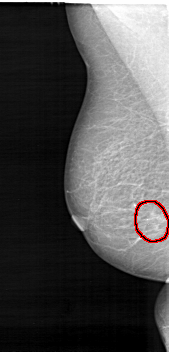

D_4103_1.RIGHT_MLO

FILE: D_4103_1.RIGHT_MLO.OVERLAY

TOTAL_ABNORMALITIES 1

ABNORMALITY 1

LESION_TYPE CALCIFICATION TYPE PUNCTATE DISTRIBUTION CLUSTERED

LESION_TYPE MASS SHAPE IRREGULAR MARGINS ILL_DEFINED

ASSESSMENT 3

SUBTLETY 3

PATHOLOGY MALIGNANT

TOTAL_OUTLINES 1

BOUNDARY